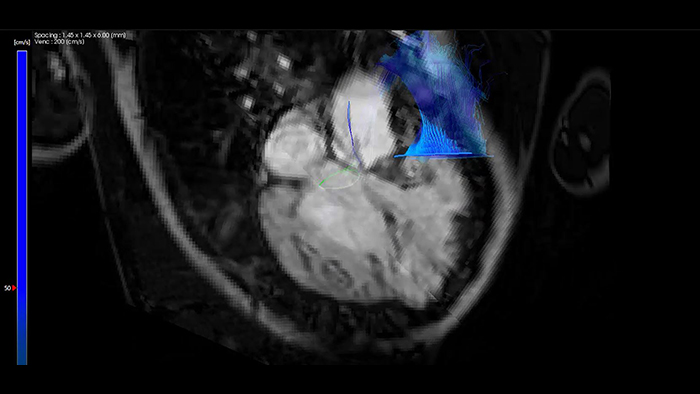

Wykorzystanie aplikacji MR Caas 4D Flow z systemu IntelliSpace Portal w obrazowaniu u pacjenta z tetralogią Fallota